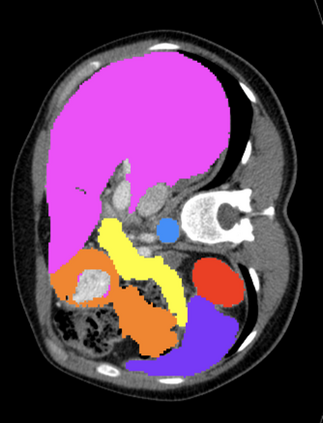

Most recent semantic segmentation methods adopt a U-Net framework with an encoder-decoder architecture. It is still challenging for U-Net with a simple skip connection scheme to model the global multi-scale context: 1) Not each skip connection setting is effective due to the issue of incompatible feature sets of encoder and decoder stage, even some skip connection negatively influence the segmentation performance; 2) The original U-Net is worse than the one without any skip connection on some datasets. Based on our findings, we propose a new segmentation framework, named UCTransNet (with a proposed CTrans module in U-Net), from the channel perspective with attention mechanism. Specifically, the CTrans module is an alternate of the U-Net skip connections, which consists of a sub-module to conduct the multi-scale Channel Cross fusion with Transformer (named CCT) and a sub-module Channel-wise Cross-Attention (named CCA) to guide the fused multi-scale channel-wise information to effectively connect to the decoder features for eliminating the ambiguity. Hence, the proposed connection consisting of the CCT and CCA is able to replace the original skip connection to solve the semantic gaps for an accurate automatic medical image segmentation. The experimental results suggest that our UCTransNet produces more precise segmentation performance and achieves consistent improvements over the state-of-the-art for semantic segmentation across different datasets and conventional architectures involving transformer or U-shaped framework. Code: https://github.com/McGregorWwww/UCTransNet.